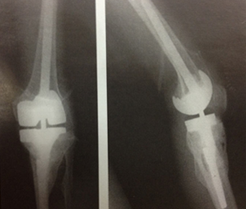

무릎이 류마티스 관절염, 골관절염 혹은 외상 후 관절염으로 인해 관절염이 생긴 경우 인공관절 치환술을 권유하게 됩니다. 치환술은 통증을 완화시키고 좀더 활동적인 삶을 유리할 수 있도록 합니다. 수술 중에 손상된 관절을 제거 하고 인공 금속 보형물로 대체하게 됩니다. 물론 전치환술이 가장 보편적인 치환술 방법이지만 어느 부분의 환자들에게는 부분 치환술이 도움이 되기도 합니다.

• 부분 인공관절 보형물

전치환술의 보형물은 대퇴골과 경골을 표면을 전체적으로 덮는 큰 보형물이지만 한 구획만 손상 입었을 경우 그 구획만 교체할 수 있는 작은 보형물입니다.

인공관절 이미지